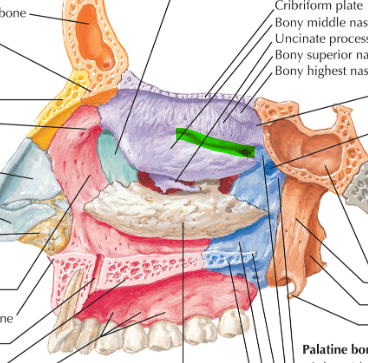

Hueso Etmoides

Parte anterior y media de la base del cráneo

Forma parte de las fosas nasales, cavidades orbitarias y craneal

Lámina vertical del etmoides

Lámina perpendicular del etmoides

Forma parte del tabique de separación de ambas fosas nasales (septum/tabique nasal)

Apófisis crista galli por arriba de la lámina horizontal

Apófisis crista galli

Triangular, borde anterior bajo articula con el hueso frontal y completan el agujero ciego(foramen cecum) entre surcos

Lámina cribosa del etmoides

Forma parte del piso de la fosa craneal anterior

Perforada por múltiples orificios, por eso el nombre de cribiforme

Dos apófisis alares que articulan con el frontal, creando el foramen cecum

Cornete nasal superior

Cornete nasal medio

Laberintos Etmoidales

Contiene los cornetes superiores y medios

Forma parte de la pared lateral de las fosas nasales

Lámina papirácea en cara lateral

Lámina papirácea del etmoides

Cara orbitaria del etmoides

Forma una gran parte de la pared medial de la órbita